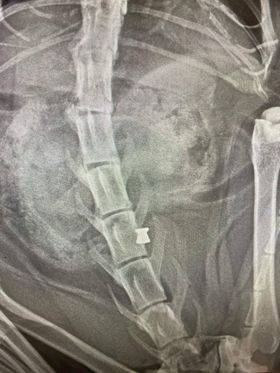

»Gre za mojo mačko. Pred dvema mesecema sem opazila rano na njenem hrbtu. Rana se je zacelila, vendar je ostala bula.

Šla sem k svojemu veterinarju, kjer so opravili rentgen. Ta je pokazal, da ima moj muc v sebi naboj zračne puške,« pravi bralka.

Naboj se je nahajal na zadnjem delu hrbtenice, zato je bila včeraj potrebna operacija.